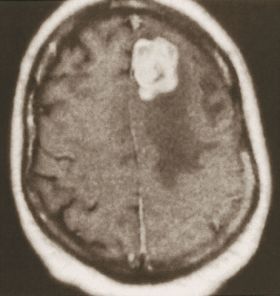

الشكل (2) صورة مرنان مغنطيسي للدماغ تظهر وجود ورم انتقالي دماغي (الكتلة البيضاء) وحولها تظهر منطقة الوذمة الدماغية (ناقصة الإشارة أو «سوداء»).

ويعتمد في المرحلة الثانية من التشخيص عادة على تصوير الدماغ (بالرنين المغنطيسي أو التصوير الطبقي المحوري).

إن الوذمة في (الشكل 2) موضعة في منطقة محدودة من الدماغ حول الكتلة الورمية، أما في حال كون الوذمة الدماغية معممة فعندها تُظهر الصور الدماغية إمحاء في الأثلام وأحياناً صِغراً في حجم البطينات الدماغية نتيجة انتباج النسيج الدماغي.